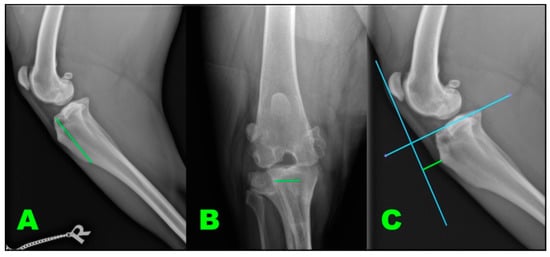

Figure 3.

Measures taken to acquire implant conformation. We take three measures (A–C) corresponding to the green in the images. (A) Implant length; (B) implant width; (C) implant depth.